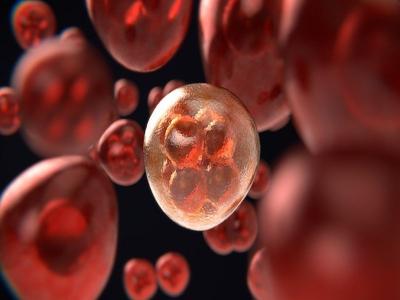

रक्त में हीमोग्लोबिन की कमी होने पर, प्रतिदिन आंवले के रस का सेवन करना काफी लाभप्रद होता है। यह शरीर में लाल रक्त कोशिकाओं के निर्माण में सहायक होता है, और खून की कमी नहीं होने देता है।